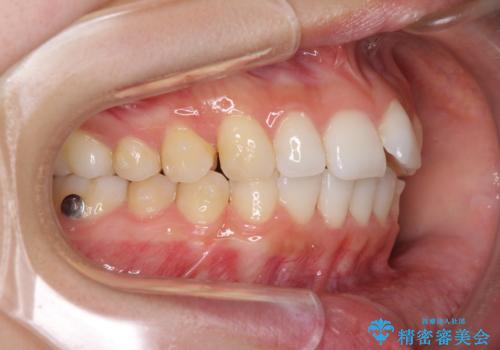

口が閉じにくい 1本飛び出した前歯の矯正治療

- 1本飛び出した前歯を治したいとのことで来院された患者様です。

歯列全体の拡大とIPR(歯と歯の間を削る)によってデコボコが解消するようにし、さらにゴムかけを活用して右側の咬み合わせ位置を変えるように設計し、インビザラインにより治療を行うこととしました。

後方移動に際し、上下顎の親知らずは3本とも抜歯することとしました。